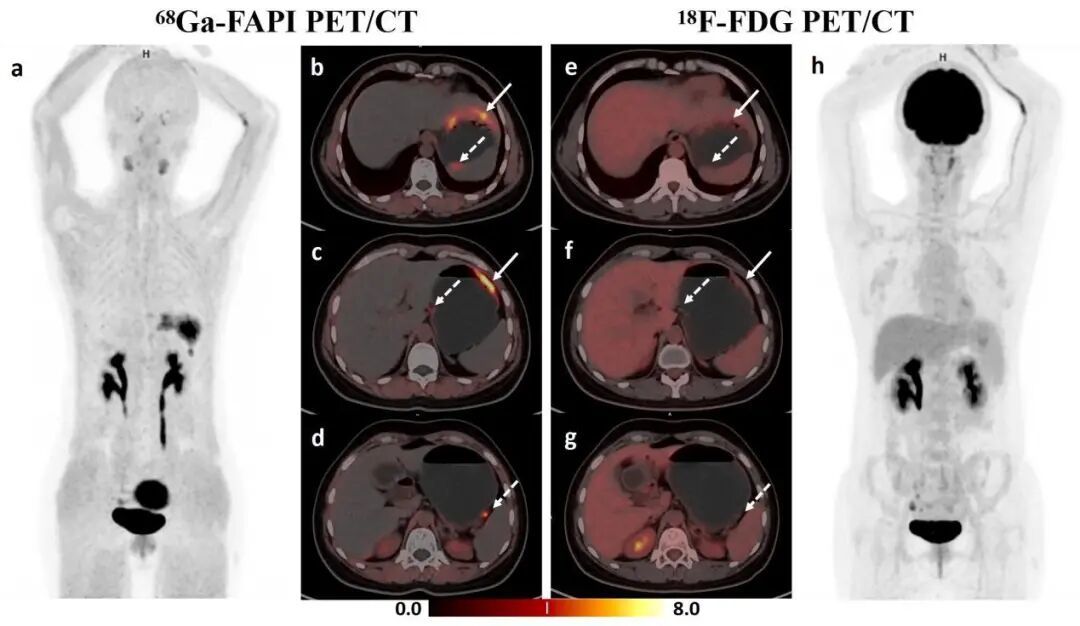

图1 68Ga-FAPI PET/CT(左图)清晰显影了在传统18F-FDG PET/CT(右图)中“隐身”的胃印戒细胞癌及胃周小转移淋巴结

1. 破解“隐身”胃癌检出难题:传统18F-FDG PET/CT主要通过捕捉肿瘤细胞异常活跃的葡萄糖代谢来探测肿瘤。然而,印戒细胞癌、黏液腺癌等亚型肿瘤细胞代谢活性低、且细胞稀疏、间质丰富,在18F-FDG PET显像中摄取微弱,如同“隐身”。68Ga-FAPI PET/CT则另辟蹊径——它专门追踪肿瘤周围被激活的 “帮凶”细胞(即肿瘤相关成纤维细胞),直接洞察肿瘤赖以生存的“土壤”,只要肿瘤存在并生长,这些“帮凶”就会大量聚集,被新技术“锁定”并显像,从而让传统影像中“隐身”的肿瘤得以清晰现形。